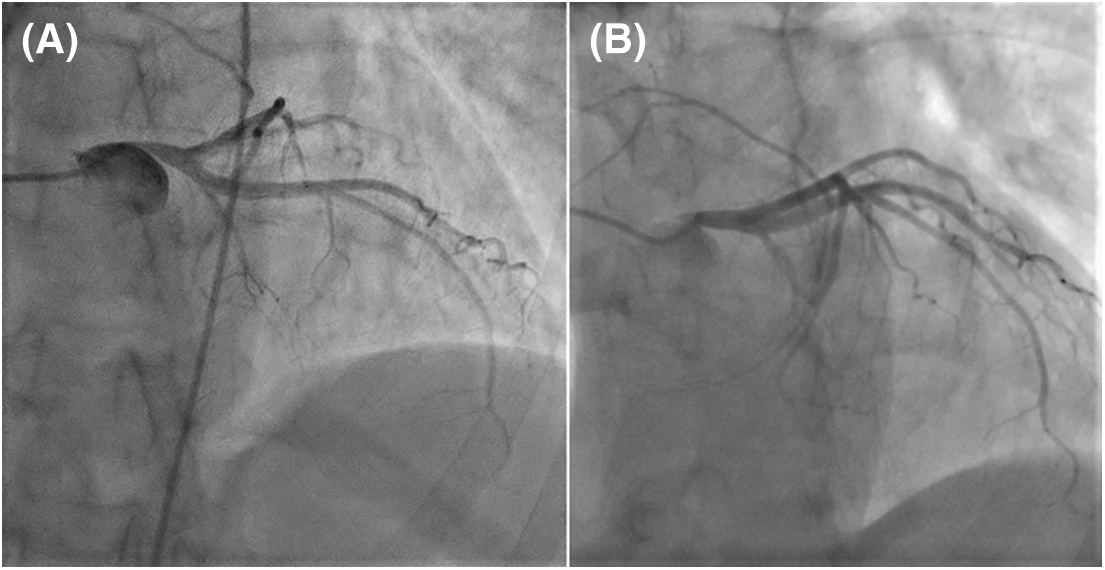

A 51-year-old female patient was referred to the cardiology unit for increasing exertional dyspnea (class III heart failure) and atypical chest pain. The patient had a large ASD, unsuitable for device closure (due to the deficient aortic and superior rims); the patient had refused surgical repair in the past. Transthoracic echocardiography (TTE) showed a large ostium secundum ASD (38 mm), dilated right heart and a PAA (diameter = 58 mm), preserved right ventricular (RV) function, mild tricuspid regurgitation, and significant PAH. The cardiac catheterization (CC) found signs of pre-capillary pulmonary hypertension. The PA pressures were elevated: systolic (PAPs) = 72 mmHg and mean (PAPm) = 39 mmHg-at a peak systemic pressure = 126 mmHg; pulmonary artery wedge pressure (PAWP) = 7 mmHg; and increased pulmonary vascular resistance (PVR) = 4.3 Wood units (WU). The pulmonary and systemic vascular resistance ratio (PVR/PVS) was 0.31, and the pulmonary to systemic flow ratio (Qp/Qs) was 1.3. Nitric oxide testing showed an incomplete effect (9 mmHg decrease in PAPm). PAH-targeted therapy was prescribed before deciding if surgery was the most appropriate choice. The patient received sildenafil (3 × 20 mg/day) and diuretics. After three months, mild clinical improvement was obtained (from WHO functional class III to class II). The patient covered 400 m in the 6-minute walk test (without significant systemic desaturation at the end), and BNP was mildly increased (90 ng/L). However, CC reassessment was inconclusive (PAPs = 77 mmHg, PAPm = 41 mmHg, PVR = 4 WU, peak systemic pressure = 131 mmHg, PAWP = 8, Qp/Qs = 2). The clinical and biological parameters placed the patient in the intermediate-mortality PAH risk group; thus, treatment was supplemented with bosentan. Coronary angiography (CA) found a proximal, “pencil-like,” 90% LM stenosis (Fig. 1A); PAA aneurysm was confirmed on contrast-enhanced computed tomography (Figs. 2 and 3A), which also revealed PAAs close relationship with the downwards displaced LM origin. All findings suggested LMCS, and the patient underwent surgery.

Figure 1: Coronary angiography (CA): (A). Preoperative left CA (LAO 15° CRA 30°): Severe LMCS with 90% stenosis; LM take-off angle <30°. (B). Postoperative CA (LAO 30° CRA 30°): Non-significant LM residual stenosis (30%); less steep LM take-off angle (∼45°) (LAO–left anterior oblique; CRA–cranial)

PAH-specific dual therapy was continued postoperatively. After three months, exercise tolerance significantly improved, there was no residual shunt, reverse remodeling of the right ventricle had occurred (Fig. 4), PA diameter was 33 mm. An invasive reassessment found PAPs = 54 mmHg, PAPm = 35 mmHg, PVR = 3.3 WU, and a non-significant LM residual stenosis (30%) (Fig. 1B).